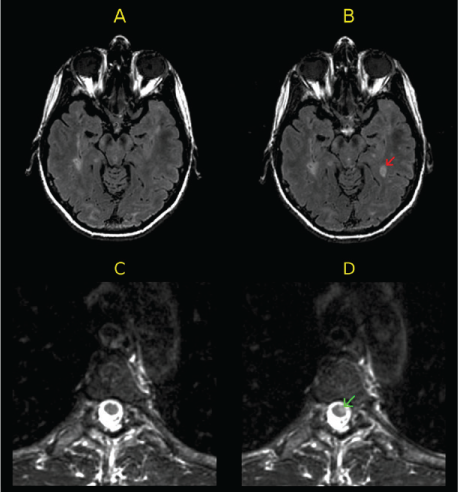

All the patients underwent brain and spinal cord MRI at baseline and follow-up using a 3T scanner (GE Signa; GE Healthcare, Milwaukee, WI). Follow-up MRIs were obtained a mean ± SD of 12.4 ± 1.3 months (range, 9.7–15.2 months) after baseline. Brain and cervical images were obtained at both time points. Fifty patients also underwent thoracic spine imaging at both time points. The following imaging parameters were relevant to the present study: axial T2-weighted fluid-attenuated inversion recovery images of the brain (repetition time [TR] = 9000 milliseconds, echo time [TE] = 151 milliseconds, inversion time = 2250 milliseconds, pixel size = 0.976 × 0.976 × 2 mm; no interslice gaps), axial T2-weighted fast spin echo (FSE) images of the spinal cord (TR = 6166.66 milliseconds, TE = 110.24 milliseconds, voxel size = 0.937 × 0.937 × 3 mm; no interslice gaps), and sagittal T2-weighted FSE images of the spinal cord (TR = 3000 milliseconds, TE = 145.66 milliseconds, voxel size = 0.859 × 0.859 × 3 mm; no interslice gaps). Sample images are shown in Figure 1. Due to scan time limitations and the fact that these were research-related scans, intravenous gadolinium was not administered.

Examples of active magnetic resonance images (MRIs) at follow-up

An experienced observer (ST) analyzed baseline and follow-up images concurrently using Jim software, version 7 (Xinapse Systems, West Bergholt, UK). Uncertain cases were reviewed by a senior observer (RB). Image window width and level were adjusted by the observer to ensure a consistent comparison between the two time points. The follow-up images were categorized qualitatively as active by the presence of either new or enlarging T2 hyperintense lesions. Thus, achieving NEDA by MRI was defined as no new or enlarging T2 hyperintense lesions. Examples of disease activity in the brain and spinal cord are shown in Figure 1.

Comparisons of patients achieving NEDA based on brain and spinal cord lesions are shown in Tables 1 and 2. Based on this sample of 61 patients, 63.9% (n = 39; 95% CI, 50.6%–75.8%) maintained NEDA in terms of brain MRI, whereas 90.2% (n = 55; 95% CI, 79.8%–96.3%) maintained NEDA based on spinal cord MRI. Thirty-eight patients achieved NEDA based on both brain and spinal cord MRI, and five patients had disease activity on both measures. Six patients had new spinal cord activity with new lesions at follow-up in the cervical only (n = 2), thoracic only (n = 3), or both (n = 1) regions of the spinal cord. The following spinal cord locations were involved with these new lesions: C2, C7, T6, T6–T7, T8–T9, and C4–C6, T4–T5, and T6 (Figure 1). Patients with disease activity in either the brain or spinal cord only were significantly more likely to have disease activity in the brain (P = .0001). In addition, only 1 of 39 patients who had NEDA based on brain MRI was identified as having disease activity based on the spinal cord (2.6%; 95% CI, 0.1%–13.5%), which can be considered the false-positive rate for NEDA based on the brain. However, this patient also had a clinical relapse that coincided with the new spinal cord activity. Thus, there was no case in which failure of NEDA was shown by spinal cord MRI alone. In total, there were seven patients with enlarging lesions, six of whom also had new lesions. At baseline, 34 patients (55.7%) had spinal cord lesions; 1 additional patient developed spinal cord involvement at follow-up.